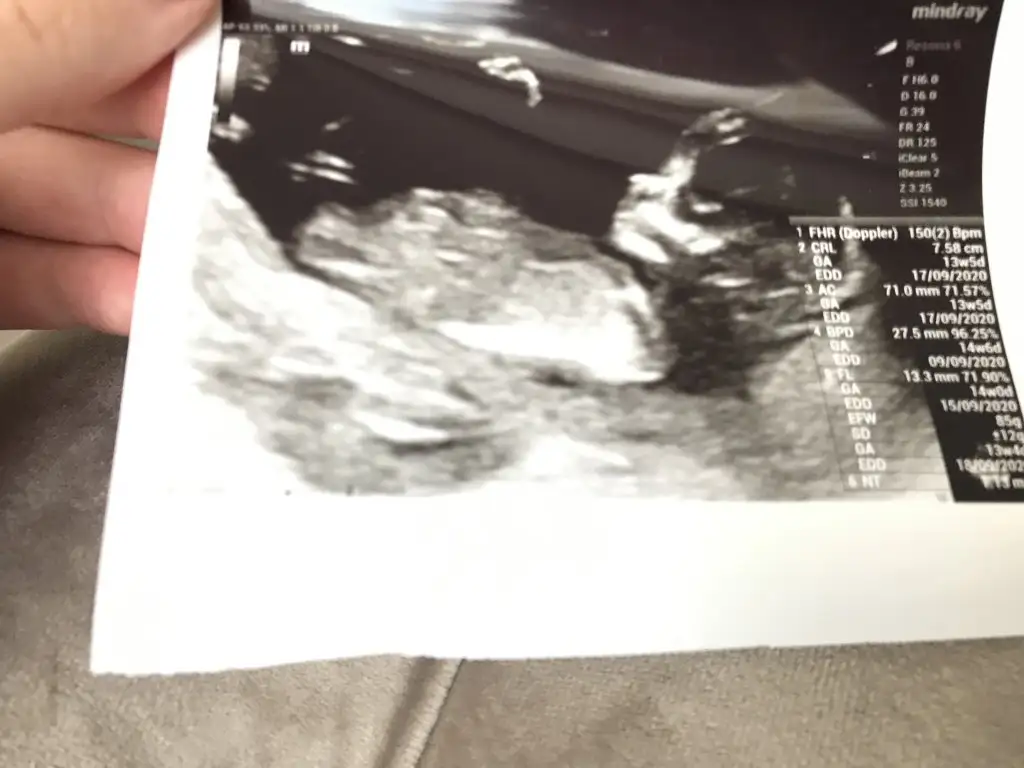

Merhabalar, ctesi ikili test icin gittim 11+6 idim. Suana kadar hep haftayla uyumlu giderdi sat. Ama bu sefer 12+6 cıktım. Yine de cinsiyet yorumlar mısınız? Gec mi kaldım? Bir de doktor tahminini söyledi ama emin değil. Kafanız karışmasın diye en son söyleyeceğim.

Eklentiler